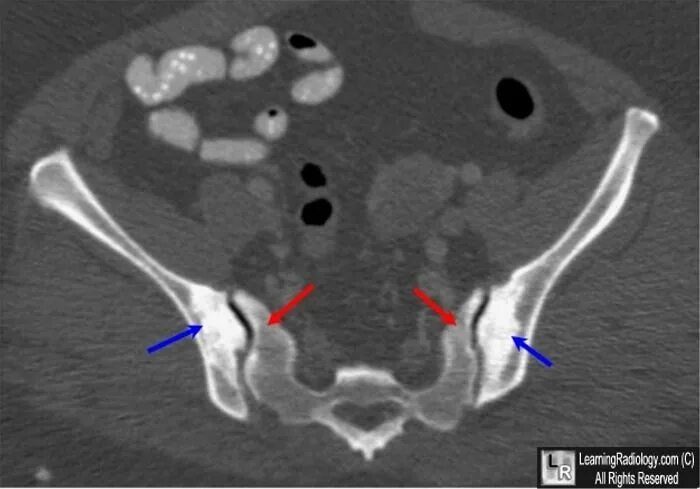

Сакроилеит на кт